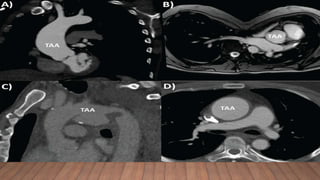

AORTIC DISEASE

• Aortic root disease, leading to aneurysmal dilatation, aortic

regurgitation, and dissection - main cause of morbidity and mortality

• Aortic enlargement is typically located at the level of sinuses of

Valsalva and may eventually extend to the sinotubular junction and

proximal ascending aorta

• Dilatation may also involve other segments of the thoracic aorta,

the abdominal aorta, the root of the pulmonary artery or even the

carotid and intracranial arteries.

• In the instance of poor echocardiographic windows, magnetic resonance

imaging (MRI) or computed tomography (CT) angiograms should be

performed.

• Routine CT or MRI imaging of the entire thoracic aorta is recommended in

patients who present with descending aortic dilation, type B aortic

dissection, or following ascending aortic aneurysm repair